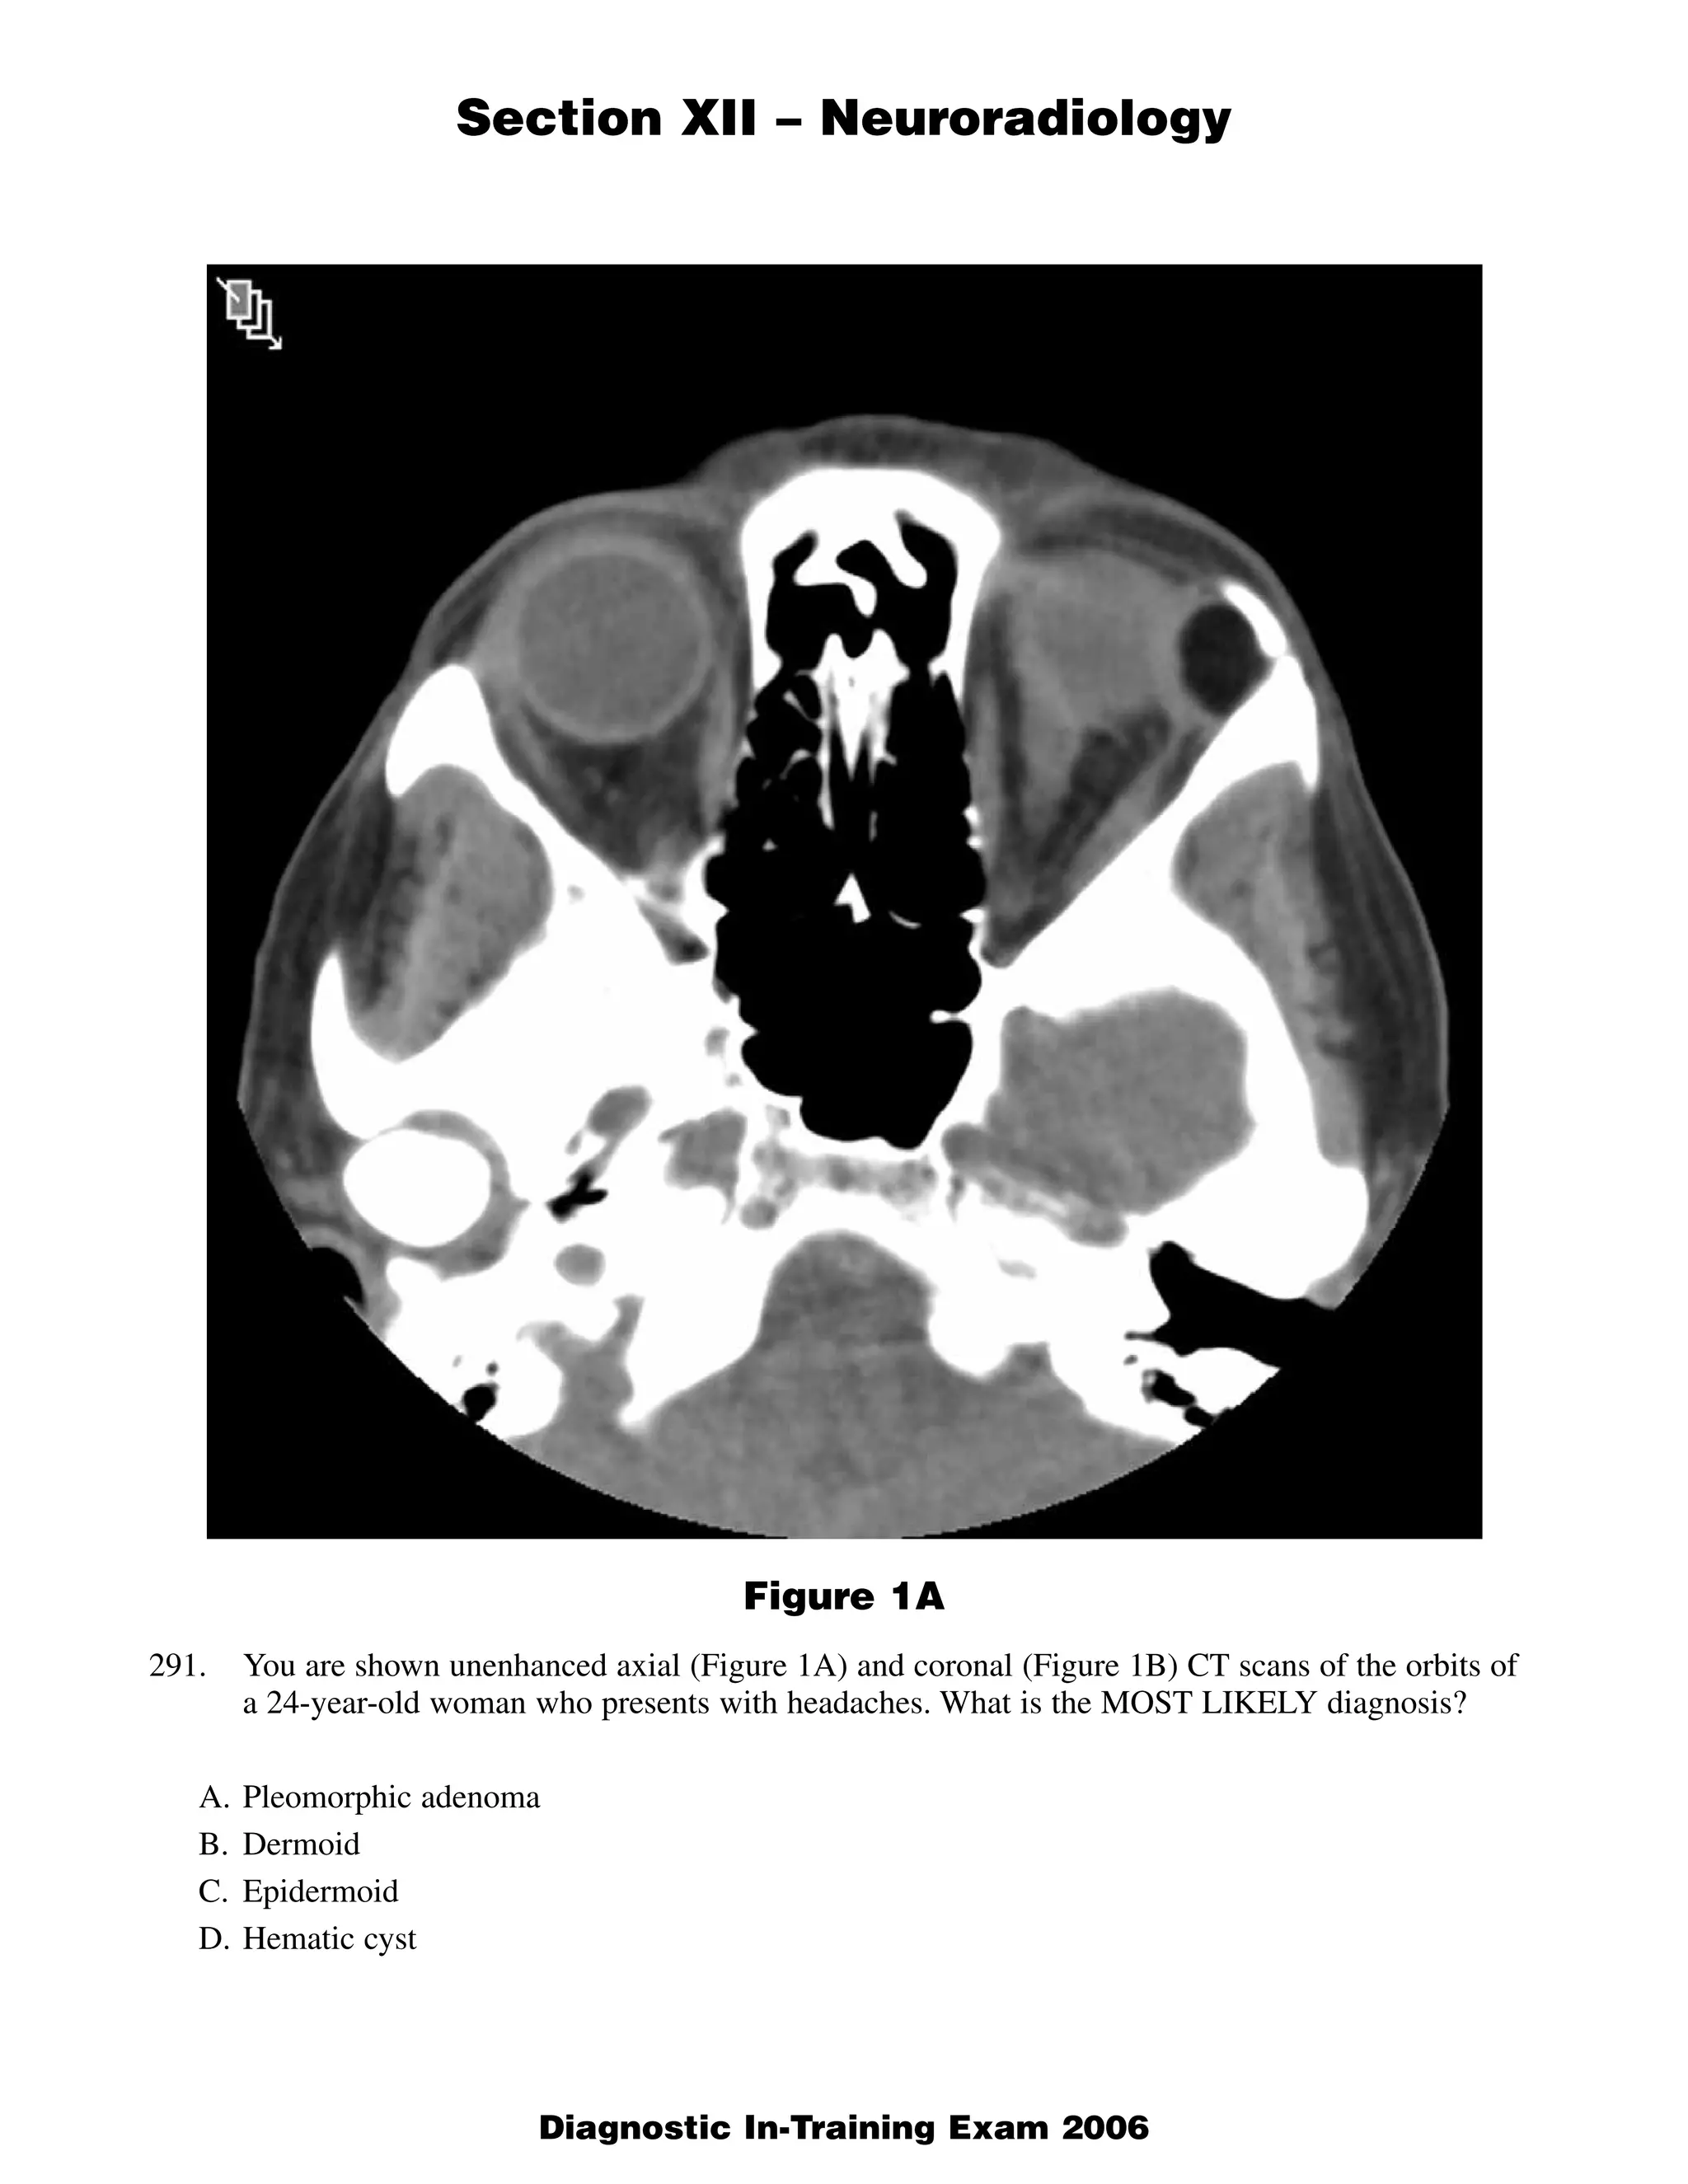

The document discusses several radiology cases involving the brain and spine. Question 291 presents CT scans of a woman with headaches and asks for the most likely diagnosis of a fat-containing extraconal orbital mass. Question 292 shows MR images of a woman with extremity weakness and asks for the most likely diagnosis of multiple brain and spine lesions. Question 293 presents MR images of a man with back pain and asks for the diagnosis of a posterior spinal mass seen on the images.